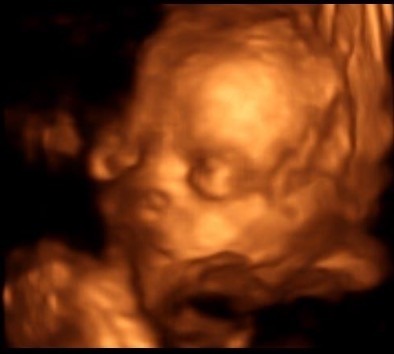

Had our 4D scan yesterday now DH is finally home and she looks exactly like her big brother Smile

BiffleRoo · 15/03/2016 07:21

Helps if I attach the picture!

Wow!!! Amazing picture!

Great pic biffle

What a gorgeous scan biffle ... Makes me want to go for a 4D one now too but DH will never agree.